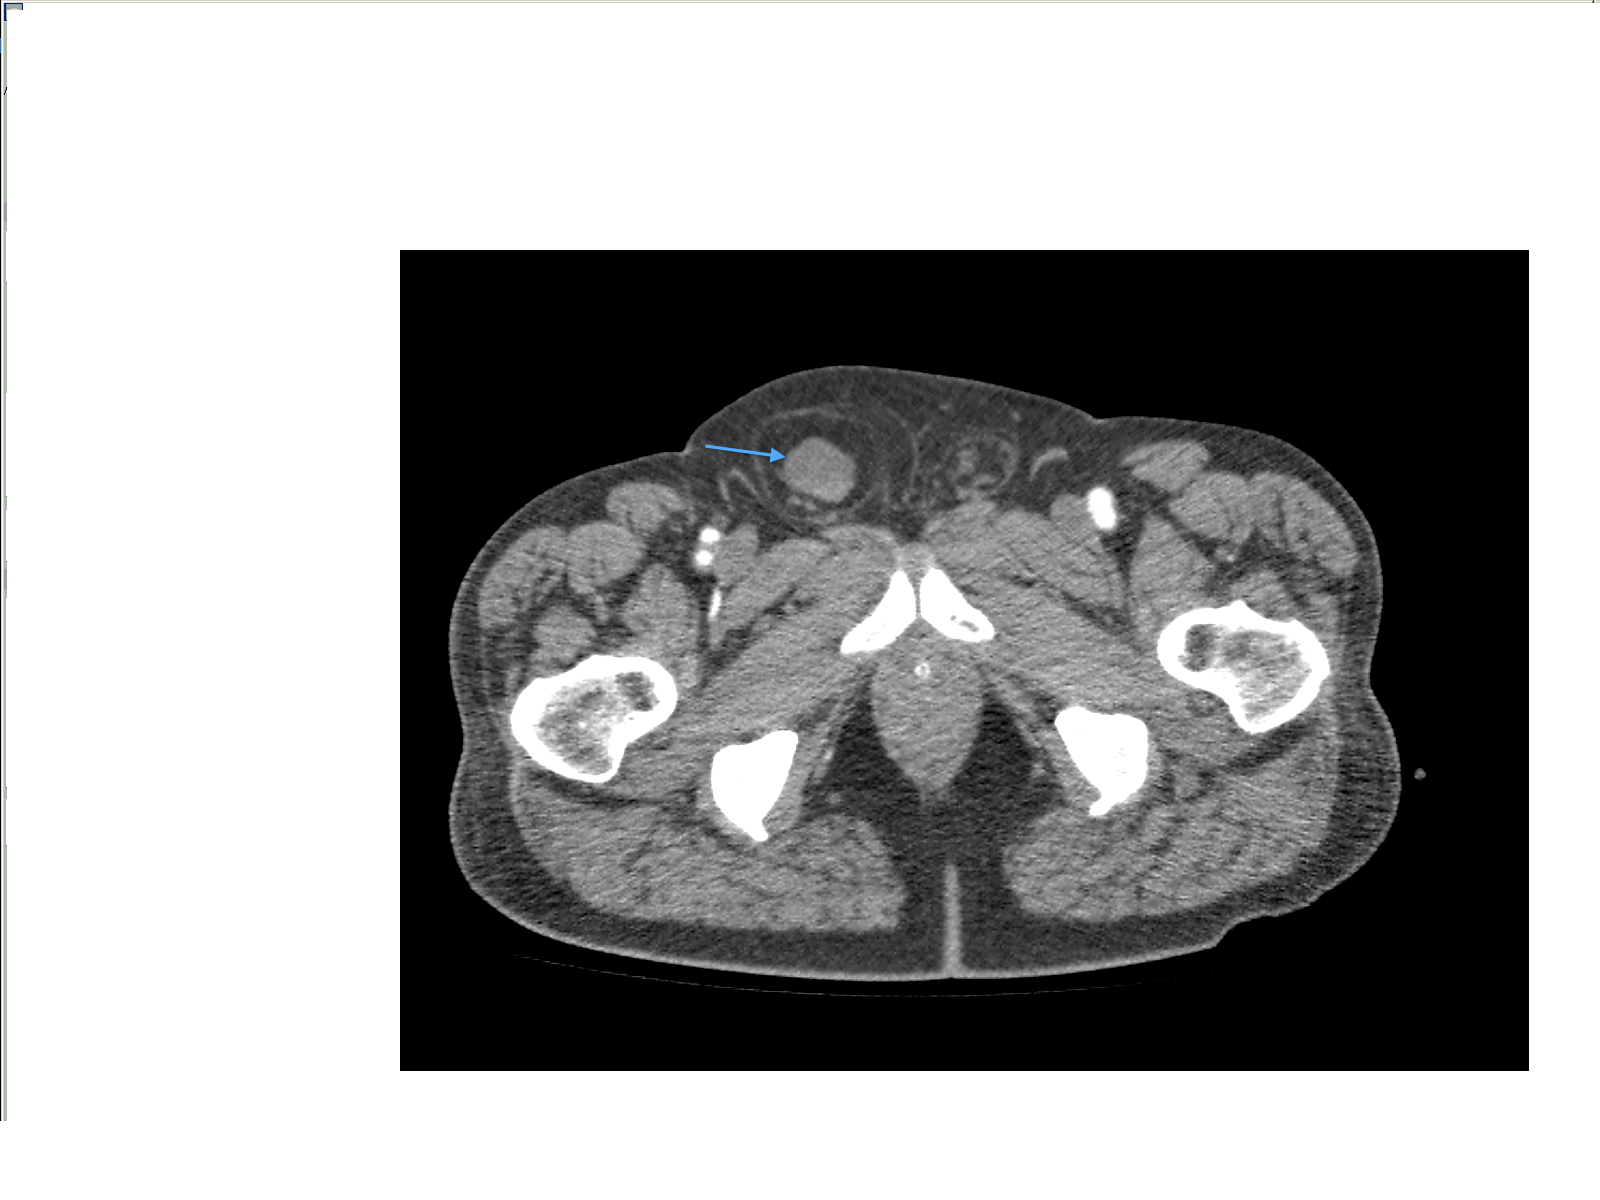

Small bowel obstruction is a common clinical presentation that presents a diagnostic conundrum. Over the last 2 decades, there has been a paradigm shift in the radiological investigation of small bowel obstruction (SBO) and in the indication for and timing of surgical intervention. Cross sectional imaging (predominantly computed tomography) has largely replaced the widespread use of radiographic small bowel follow-through studies as the imaging modality of choice for SBO. This article illustrates the current imaging modalities available for diagnosis of small bowel obstruction. (Full text available online at www.medpharm.tandfonline.com/ojfp) S Afr Fam Pract 2015; DOI: /10.1080/20786190.2014.977052